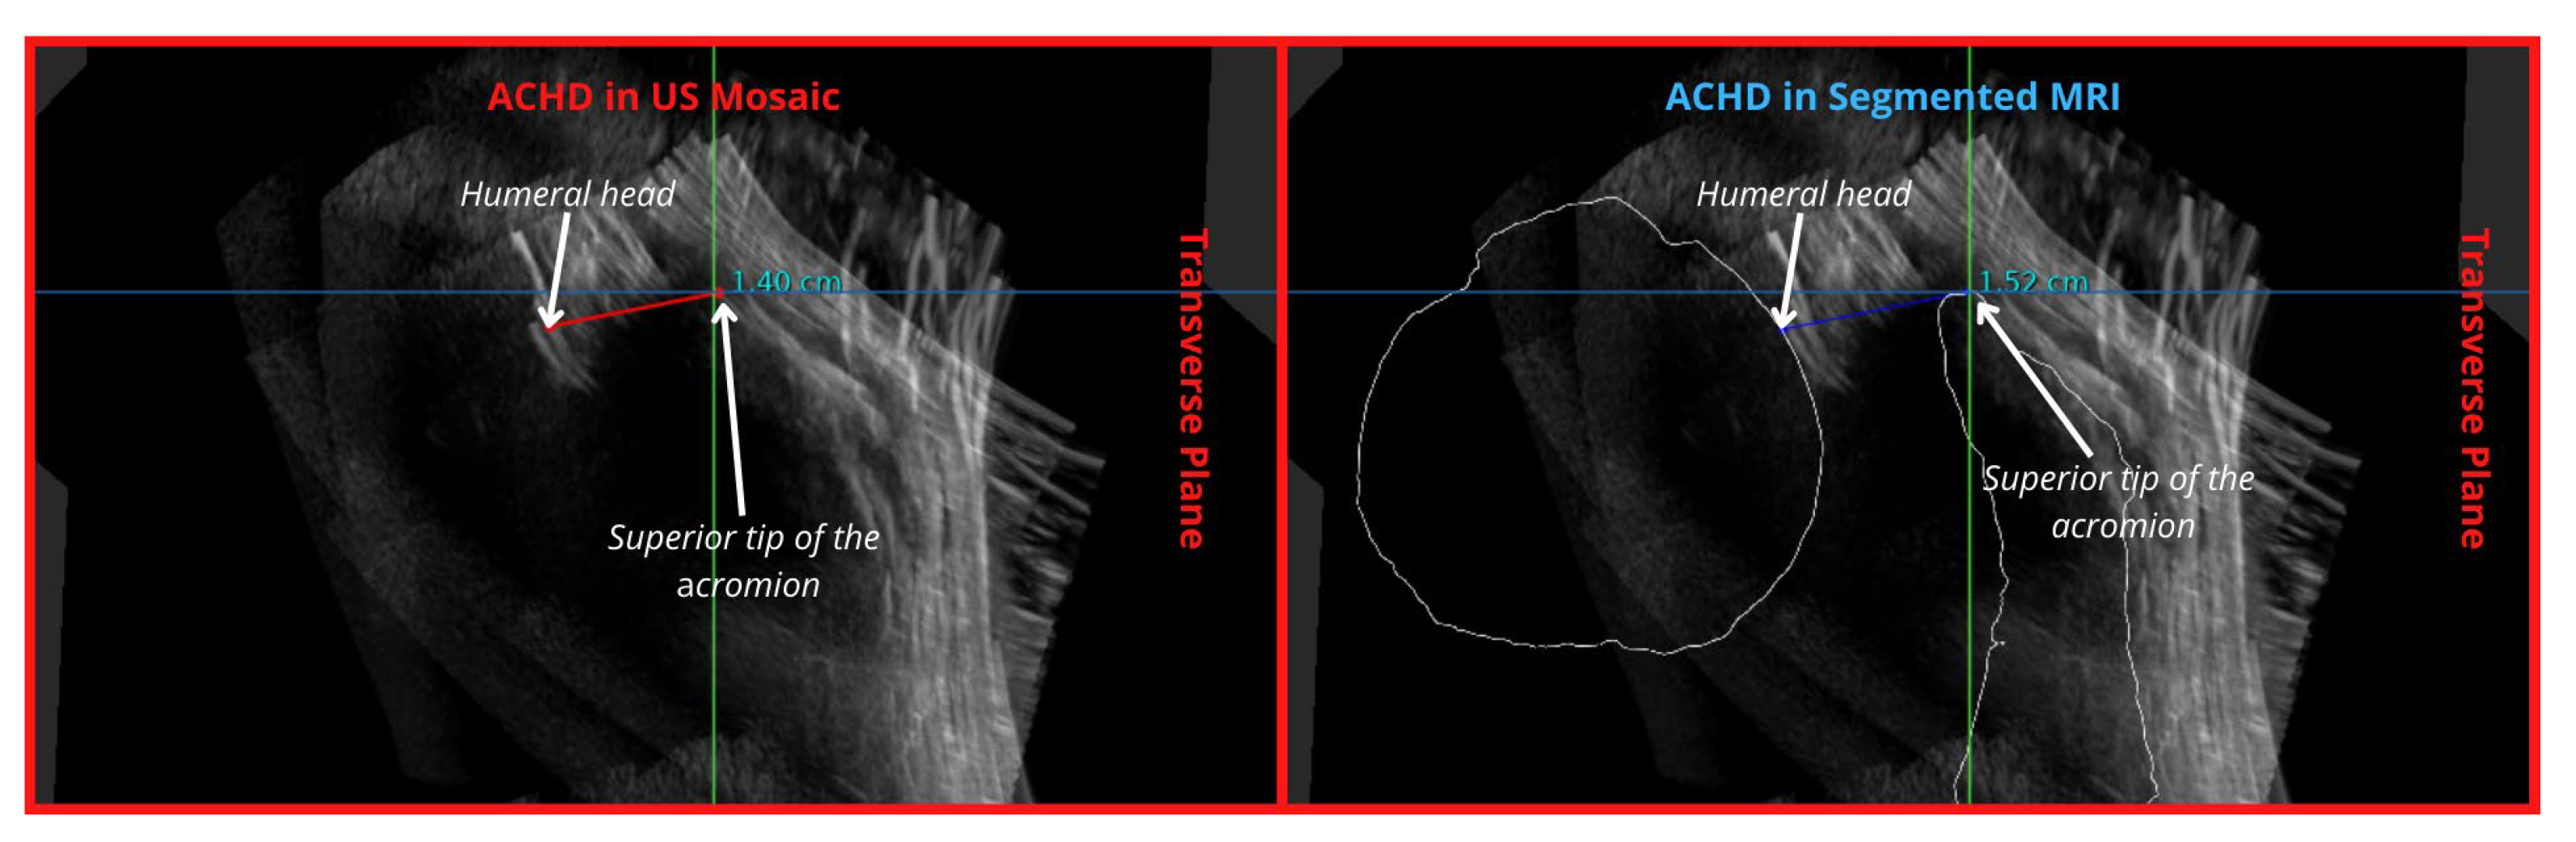

| Acromiohumeral Distance (ACHD) | 3 | Partially Demonstrated | 1 | Well demonstrated | ||

| ACHD | 3 | Humeral head not continuous at region of measurement | 1 | Easily measured with MRI bone outline | 1 | |